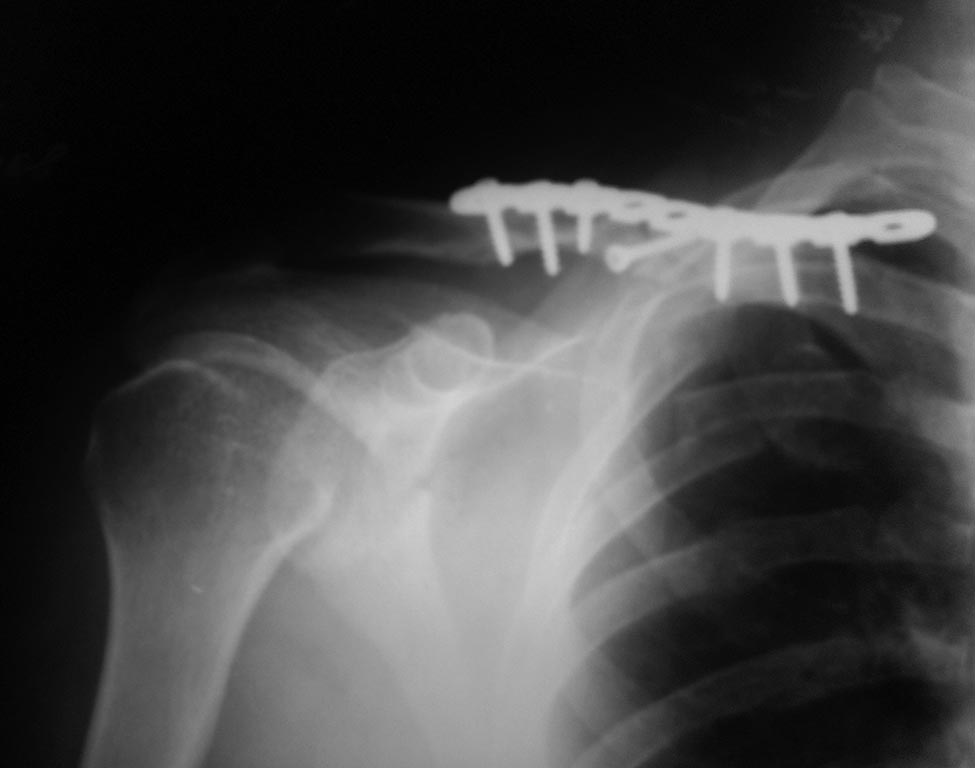

[Ortho] Последствия перелома ключицы

Пациент, 30 лет оперирован пластиной и винтами

Перелом на момент операции свежий, время операции - начало февраля 2015.

Через 1,5 мес на контрольном снимке стояние пластины удовлетворительное.

Еще через месяц - диастаз дистального конца пластины и дистального

отломка. Важно: больной не соблюдал режим, через 2 недели от момента

операции начал движения рукой.

Вопрос: Это рефрактура (как пишут рентгенологи)? Это несросшийся

перелом? Делать ли костную пластику? Спасибо!!!